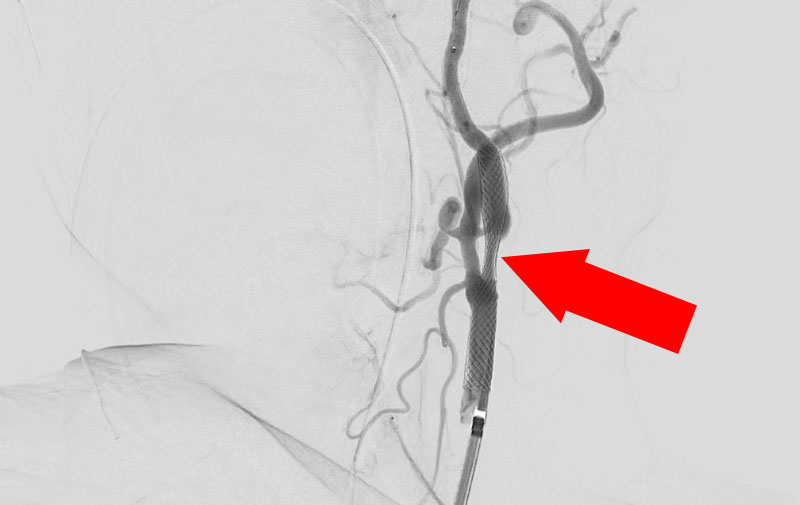

No.1191 手術前

No.1191 手術中

No.1191 手術後